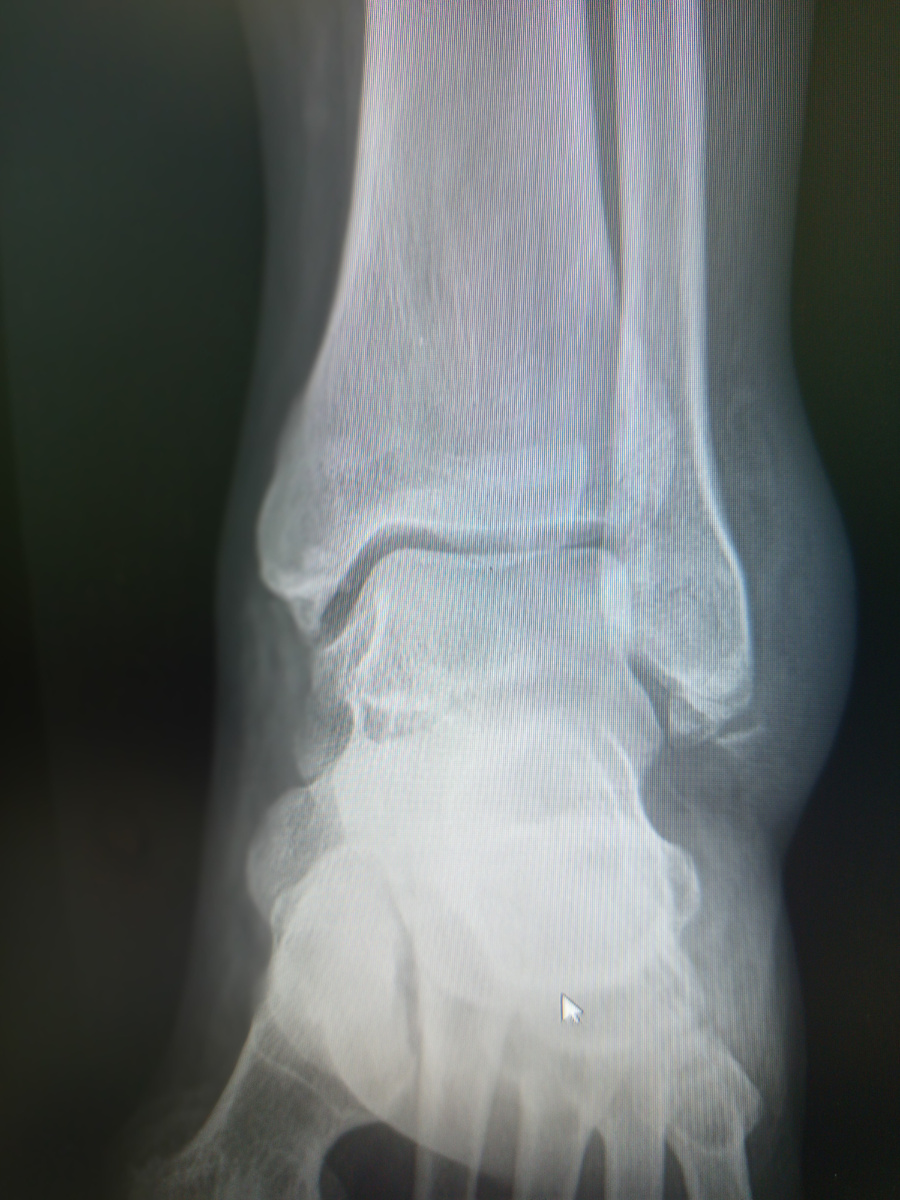

-Что же вы с такой ногой работали? –поинтересовалась я. Нога в голеностопи сильно распухшая и черного цвета вдоль линии стопы.

–А куда мне деваться было?-угрюмо ответил пациент.

А сейчас уже точно придется сидеть дома, с подтвержденным-то диагнозом.